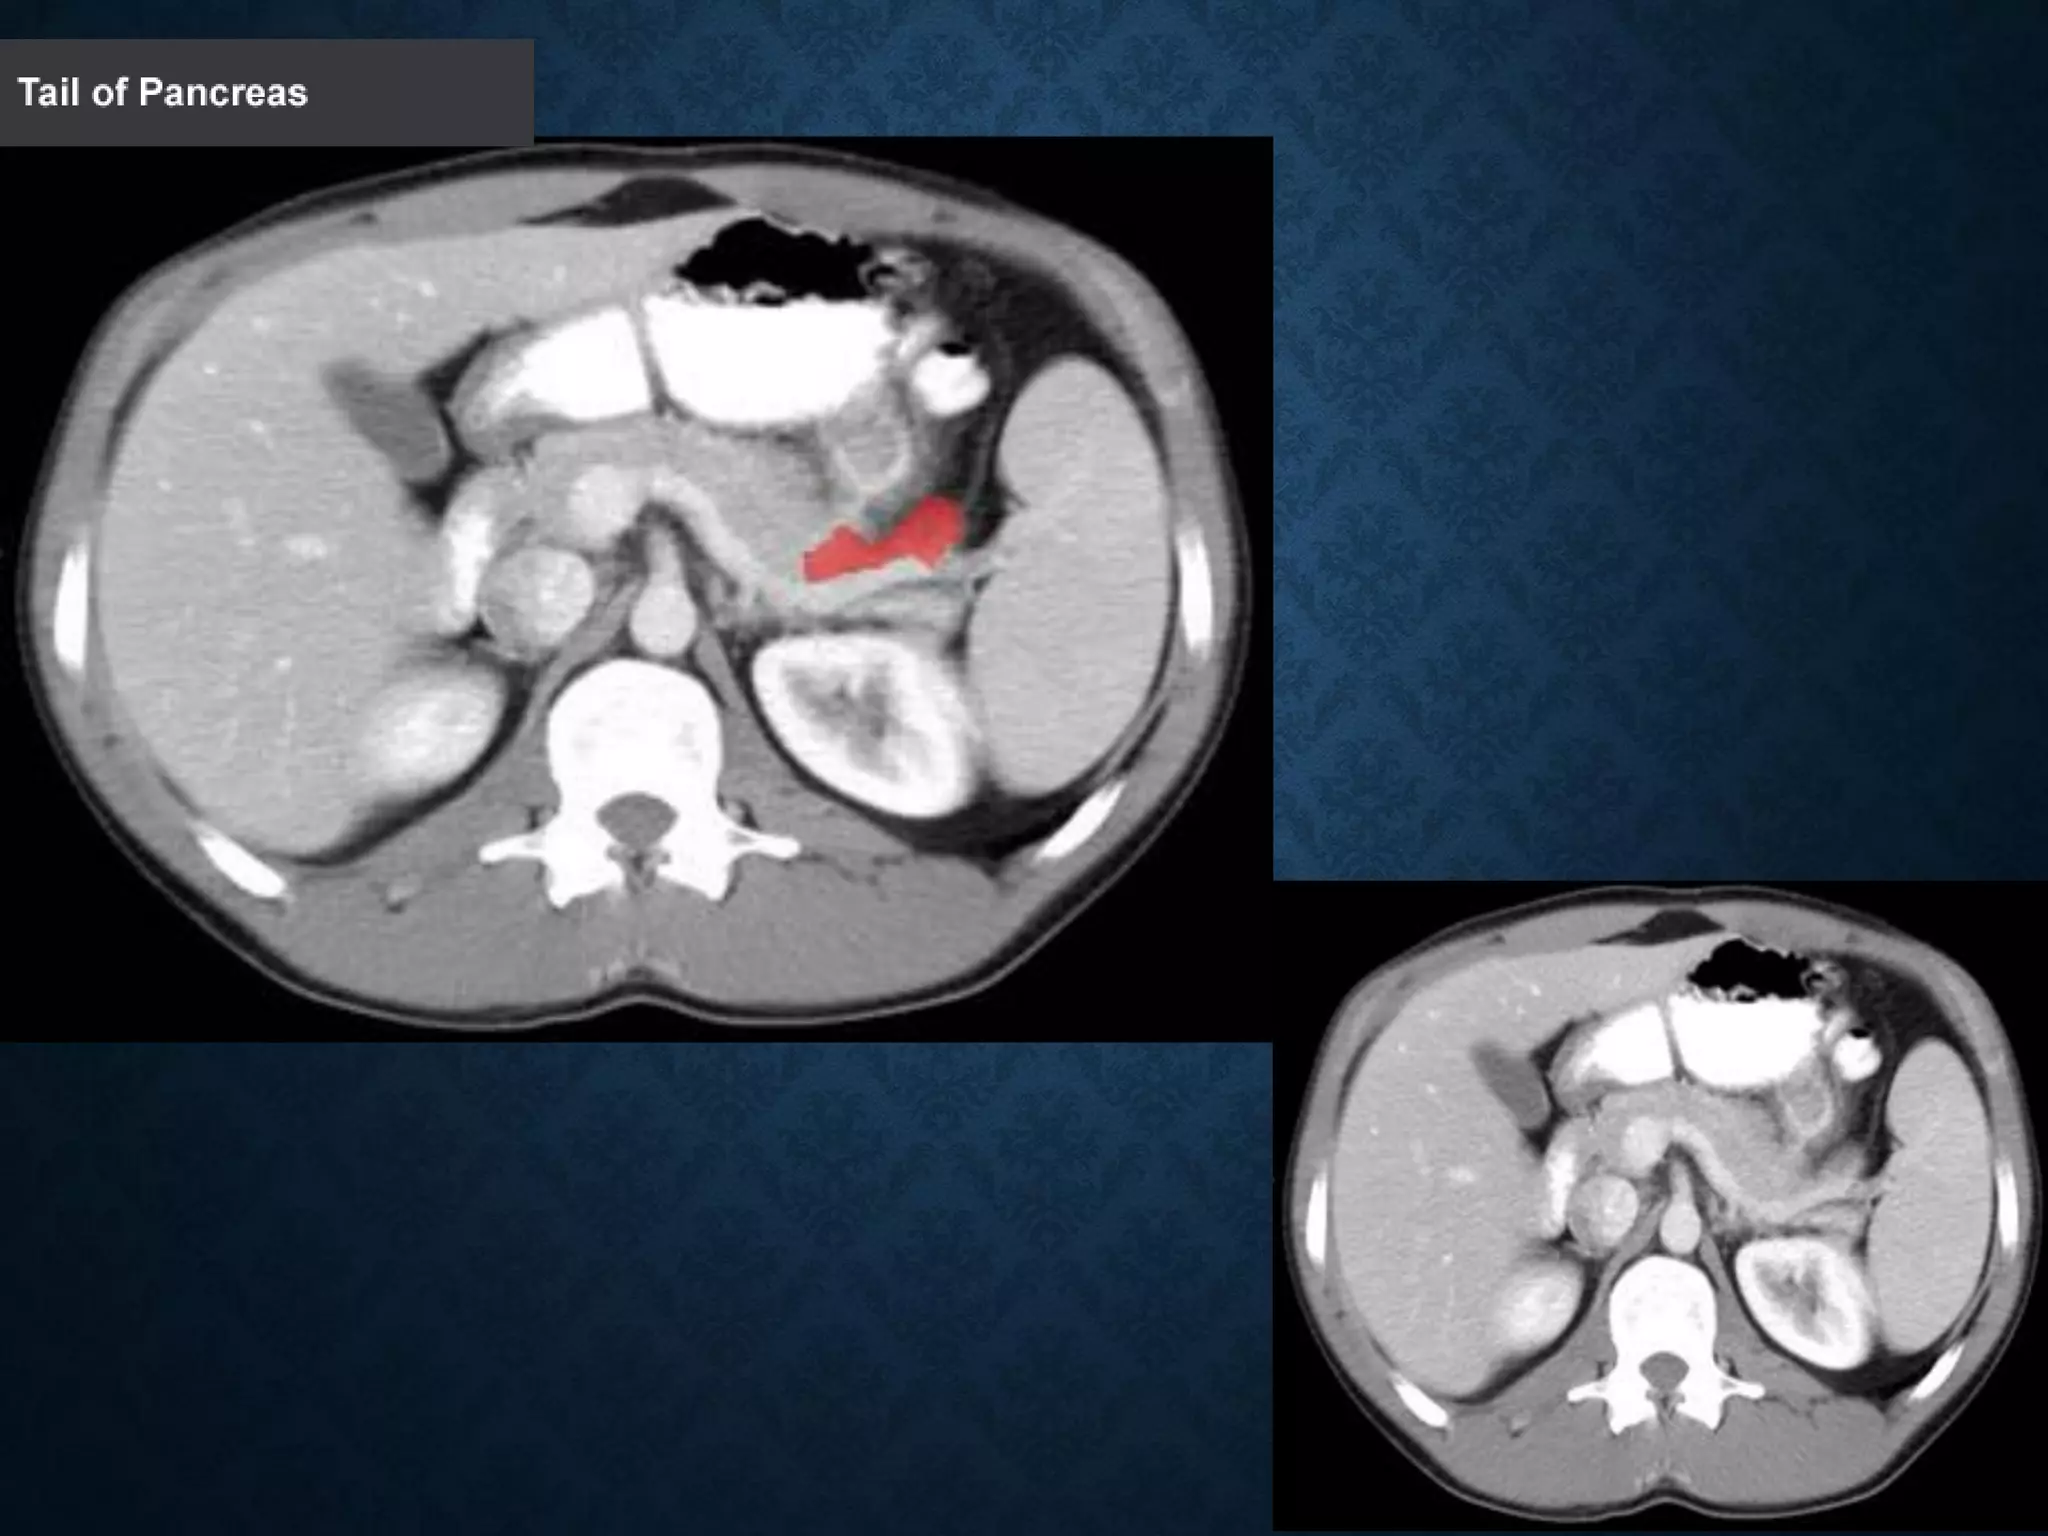

4: Body of pancreas

11:Tail of pancreas

PANCREAS 1: Head ofpancreas 2: Uncinate process of pancreas 3: Pancreatic notch 4: Body of pancreas 5: Anterior surface of pancreas 6: Inferior surface of pancreas 7: Superior margin of pancreas 8: Anterior margin of pancreas 9: Inferior margin of pancreas 10: Omental tuber 11:Tail of pancreas 12: Duodenum

1: Head ofpancreas 2: Uncinate process of pancreas 3: Pancreatic notch 4: Body of pancreas 5: Anterior surface of pancreas 6: Inferior surface of pancreas 7: Superior margin of pancreas 8: Anterior margin of pancreas 9: Inferior margin of pancreas 10: Omental tuber 11:Tail of pancreas 12: Duodenum